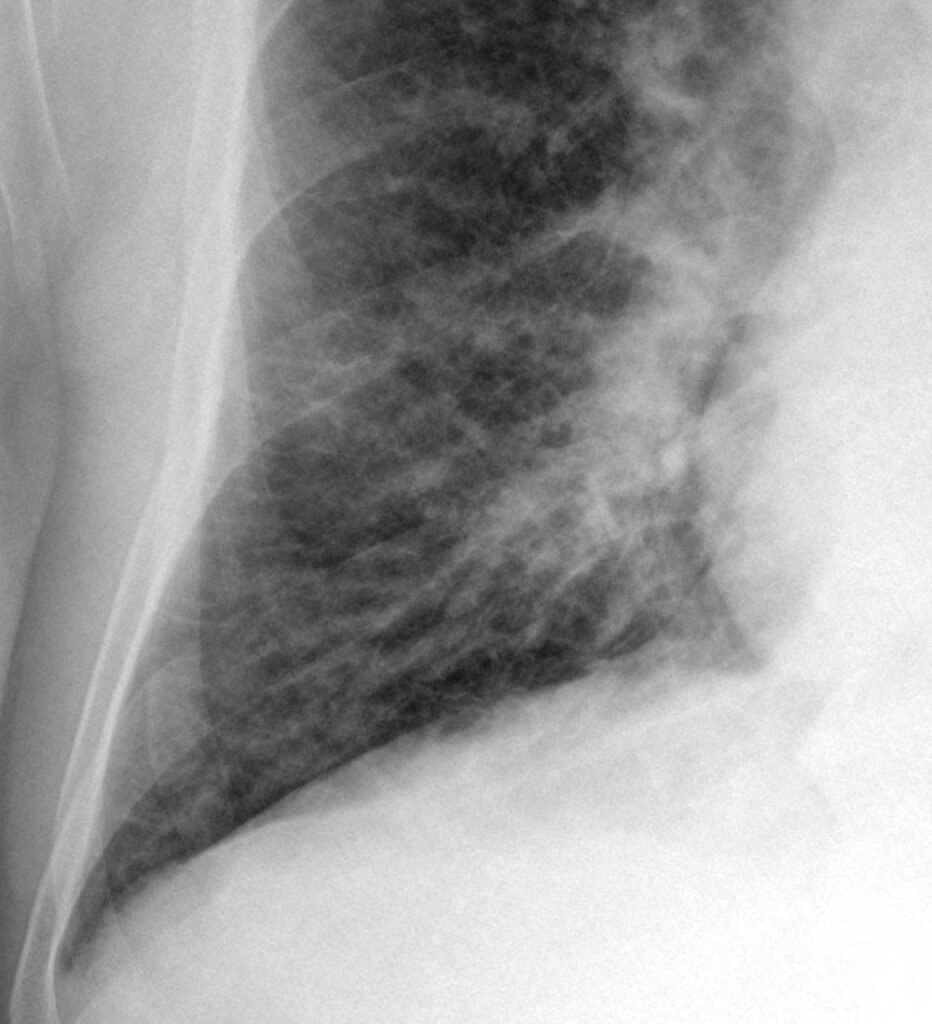

Si notino i segni di ridistribuzione vascolare verso i campi superiori e l’ingrandimento secondario alla congestione di entrambi gli ili polmonari definito “ad ali di farfalla”.

La radiografia del torace può mostrare segni di congestione interstiziale (linee di Kerley B), l’edema alveolare ad “ali di farfalla” e quote di versamento pleurico bilaterale.